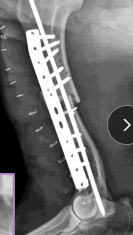

Plates

What:

Round (compression) or oval holes @ fracture line

Dynamic compression plate (DCP)

Limited-contact DCP (LC-DCP)

Locking plates: rigid plate-screw interface, for poor bone quality, less contouring needed

Why:

Compression: transverse fractures (plate/screws)

Neutralization: protects adjunct fixation (lag screw/cerclage + plate/screws)

Buttress: plate carries full load for unstable fracture

How:

Apply to tension surface of bone

Must engage ≥6 cortices on each side of fracture!!

Interlocking Nail

What: IM pin + locking bolts proximal and distal

IM pin controls bending

Bolts control shear & rotation

Why: femur, tibia, humerus: limited to

$$, technically demanding, specialized

Fills 80-90% of medullary canal

Place proximal and distal of break